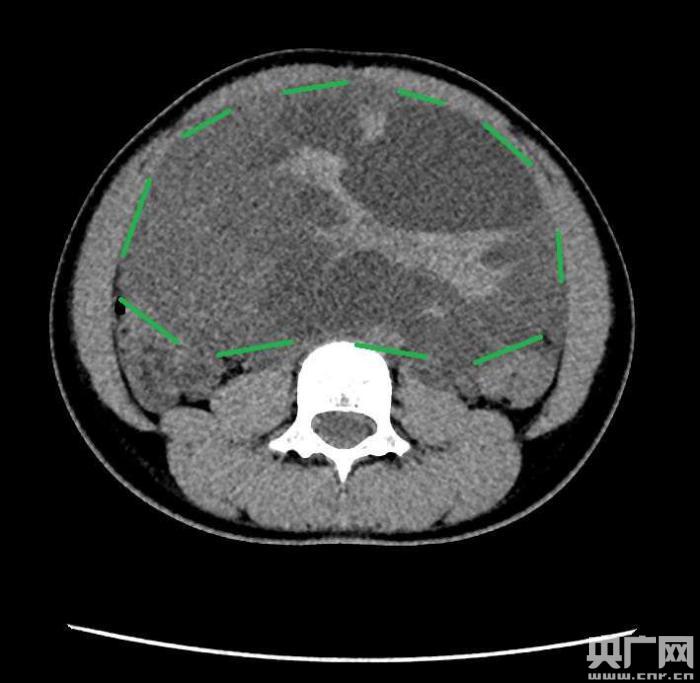

入院后,普外一科肖東主任向家長(zhǎng)詢問(wèn)了病史,仔細(xì)進(jìn)行了體格檢查,并完善腹部CT。CT結(jié)果提示,孩子的大部分腹腔、盆腔被一個(gè)巨大的腫瘤占據(jù),腸道、血管和腎盂都受到了不同程度的壓迫。從CT上看,腫瘤很可能起源于左側(cè)的卵巢。

手術(shù)中發(fā)現(xiàn),小琪腹中的腫瘤體積巨大,大小約為25×20×15厘米,表面光滑,來(lái)源于左側(cè)卵巢。醫(yī)生們首先將其與周?chē)慕M織小心剝離,然后將這個(gè)占據(jù)孩子腹腔、盆腔大部分的巨大包塊完整切除,切除腫瘤后還重建了左側(cè)卵巢。剖開(kāi)瘤體,發(fā)現(xiàn)瘤體為囊性及實(shí)性混合組成,瘤體內(nèi)部充盈著粘液狀的液體,重量達(dá)到了3000克。術(shù)后小琪病情穩(wěn)定,測(cè)量腹圍從術(shù)前的72厘米減小到了62厘米。